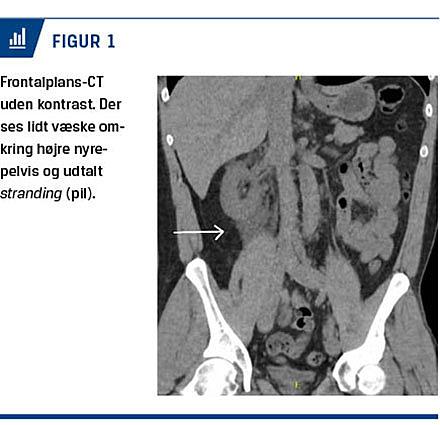

Femoghalvtreds minutter efter kontrastindløb var der fortsat meget kontrastopladning i højre nyreparenkym med kraftig opladning i pelvis (Figur 2). Her kunne en kontrastdefekt i højre pelvis og proksimale ureter identificeres. Ureter distalt herfor var normal. Venstre side var med normal kontrastudskillelse med nedløb gennem slank ureter til urinblæren uden kontrastdefekter.